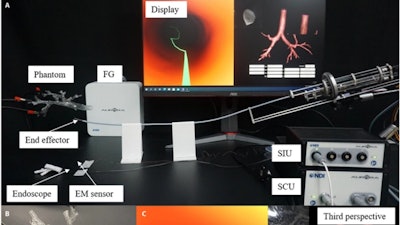

Duan and his colleagues believe the early diagnosis of lung cancer is essential for timely treatment and better prognoses. To this end, they devised a novel robotic bronchoscope system that can non-intrusively access the area of interest within the lung for minimally invasive pulmonary lesions sampling, the gold standard of lung cancer diagnoses. This research was published on Mar. 15 in the journal Cyborg and Bionic Systems.

“Another problem is that you can’t see the end effector of this line through the patient’s chest. However, to accurately approach the lesion of interest, the position and pose of the end effector must be determined in real-time.” said study authors. They addressed this problem by developing a navigation system, which attaches an endoscope and two electromagnetic sensors to the end effector, which enables online positioning for navigation and provides visual information for doctors to diagnose and sample.

The navigation system also reconstructs a three-dimensional virtual model based on computed tomography for robotic path planning, provided with the choice of the target area. Combining the flexible end effector and the navigation system, the robotic bronchoscope system can automatically reach the target lesion and provide intraoperative visual guidance for biopsy sampling.

They verified the feasibility of this robotic bronchoscope system via an ex vivo navigation-assisted intervention experiment. “During the experiment, the position displayed by the third perspective of the virtual endoscope is consistent with the position of the end effector’s tip relative to the airway phantom from visual observation. The virtual endoscope view also matches with the real video acquired by the endoscope module as expected,” said Li.